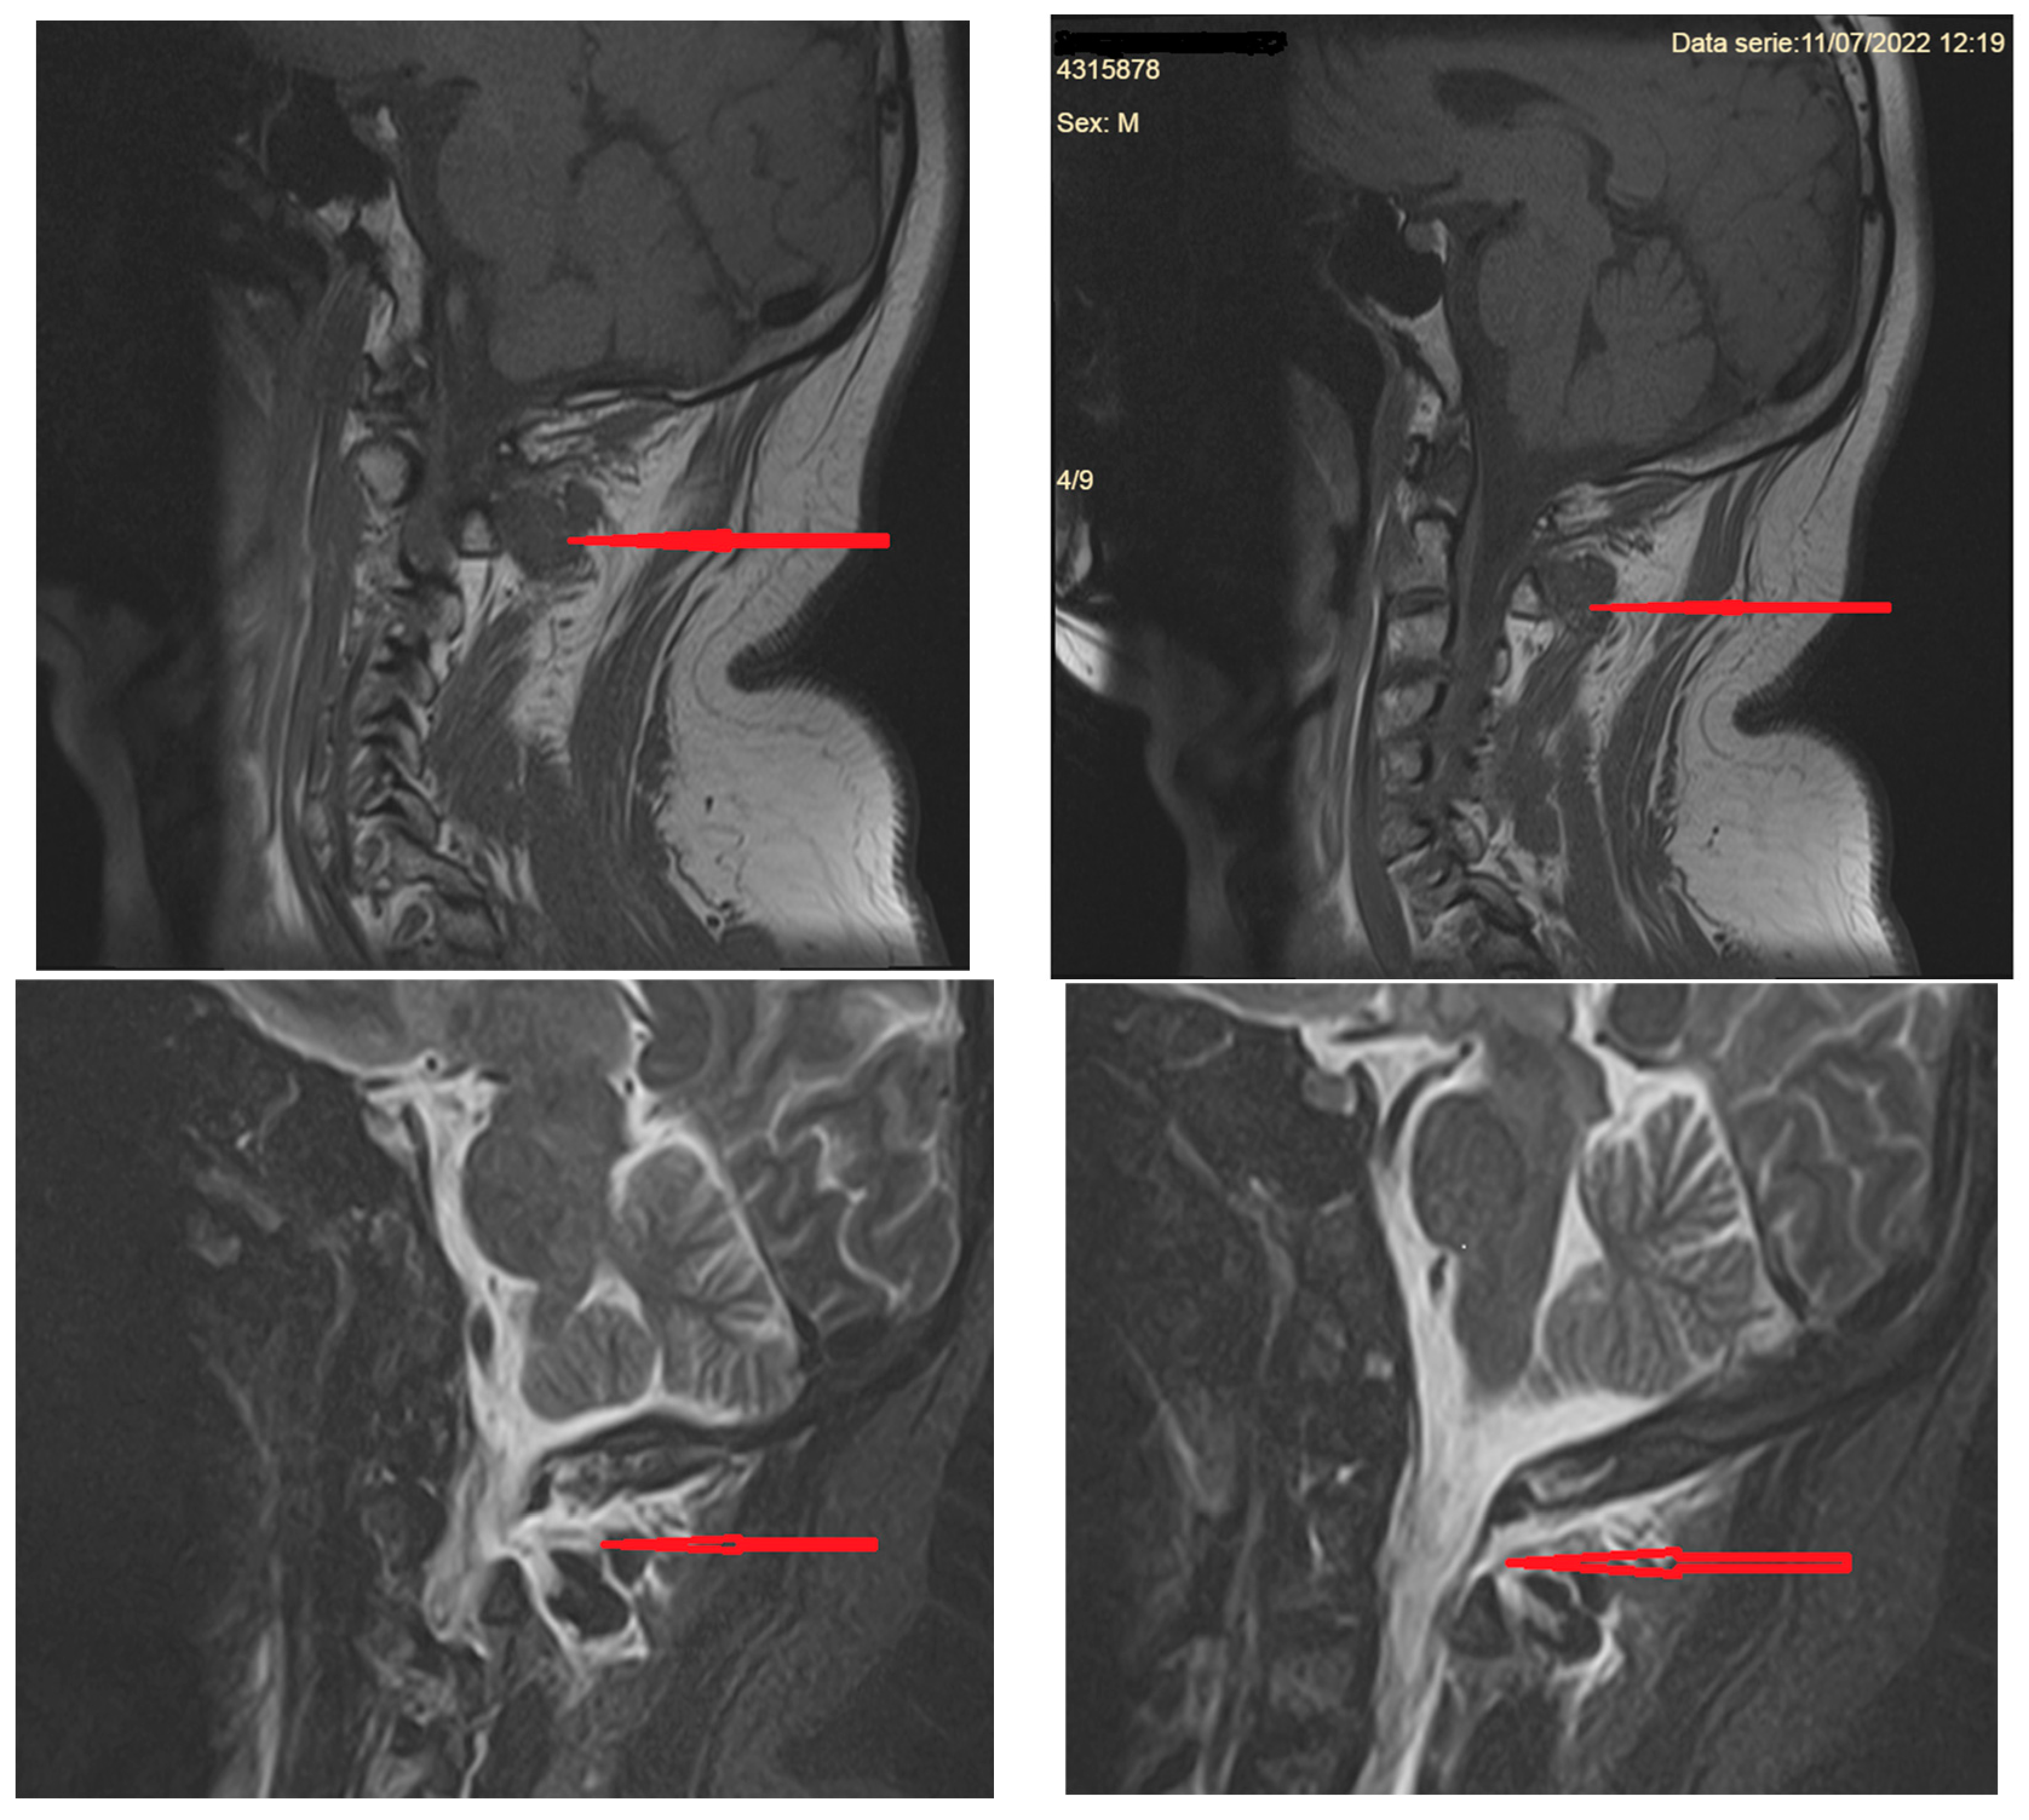

3.2.3. Imaging of the Spine

- A.

- MR imaging of the spine

- -

- Cervical pachymeningeal enhancement

- Non-compressive spinal epidural fluid collections

- Engorgement of the epidural venous plexus

- Meningeal diverticula, dilated nerve root sleeves, that can be nonspecific unless very large and irregular [40]

- Fluid collection in soft tissues near the C1–C2 vertebrae (but which sometimes may be a false CSF leak localizing sign)